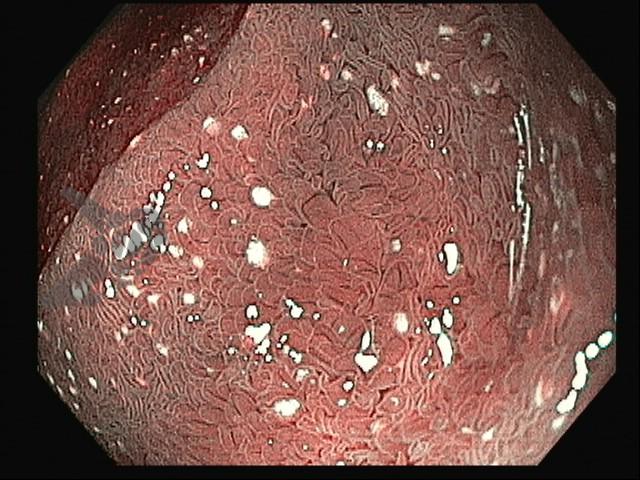

Paciente do sexo feminino, 47 anos, com história de artralgia migratória intermitente há 1 ano, queixa-se de diarreia crônica, dor abdominal e perda de peso não intencional há 3 meses. Na investigação, a Endoscopia Digestiva Alta evidenciou mucosa duodenal com áreas de vilosidades edemaciadas e presença de múltiplas placas esbranquiçadas elevadas. A avaliação histopatológica das biópsias duodenais demonstrou expansão da lâmina própria por macrófagos espumosos positivos para a coloração de Ácido Periódico de Schiff (PAS) e resistentes à diástase. A coloração de Ziehl-Neelsen resultou negativa.